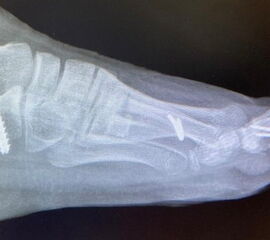

Knick-Senk-Platt-Fuß Korrektur mit dem Canalis Tarsi Spacer

In der Korrektur des schmerzhaften, aber flexiblen Knick-Senk-Fußes oder Plattfußes ist die Schraubenarthrorise mit einem Sinus tarsi oder besser bezeichnet als Canalis tarsi Spacer und alternativ mit einer Calcaneus-Stopp-Schraube seit vielen Jahren ein etabliertes Verfahren und führt zu einer kompletten Korrektur von flexiblen Knick- und Plattfuß-Fehlstellungen (Abb. 7). Die nötige Schnittlänge über dem Sinus tarsi beträgt für beide Verfahren 1 cm.